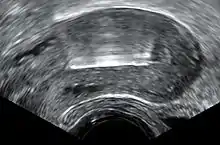

Inmediatamente antes de la inserción, el clínico realizará un examen pélvico para determinar la posición del útero.[19] Tras el examen pélvico, se mantiene abierta la vagina con un espéculo.[35] Se utiliza un tenáculo para estabilizar el cuello uterino y el útero.[35] Se puede utilizar un sonda uterina para medir la longitud y la dirección del canal cervical y el útero con el fin de disminuir el riesgo de perforación uterina. El DIU se coloca utilizando un tubo estrecho, que se introduce a través del cuello uterino hasta el útero. Unos hilos cortos de monofilamento de plástico/nylon cuelgan del útero hacia la vagina. El clínico recortará los hilos para que sólo sobresalgan 3 o 4 cm del cuello uterino y permanezcan en la parte superior de la vagina. Los hilos permiten a la paciente o al clínico comprobar periódicamente que el DIU sigue en su sitio y facilitan la extracción del dispositivo.[19]